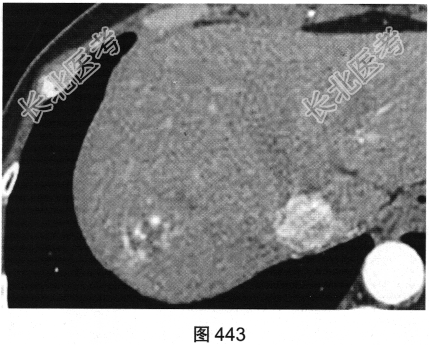

患者女性,53岁,体检经上腹部超声发现肝右叶一个稍高回声光团。查体:腹平软,右上腹无压痛,无反跳痛,肝脾肋下未及,Murphy征阴性,肝浊音界存在,肝上界位于右锁骨中线第五肋间,肝区无叩击痛,移动性浊音阴性。实验室检查:肝功能未见异常,AFP(—)。患者进一步行上腹部CT检查,如图442~图445所示。

- 多项选择题1.请问CT图像中可见哪些影像学发现( )

D、增强扫描动脉期病灶边缘结节状强化,强化程度与血管接近

F、增强扫描门脉期及延迟期强化范围向病变中心逐渐扩展